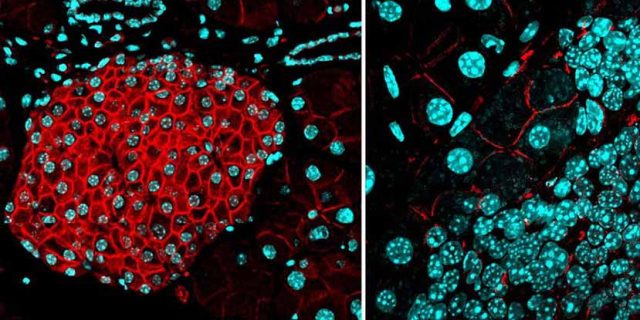

Menghentikan Penyebaran Kanker Pada Tikus Berhasil Dilakukan Ilmuwan

Salah satu tantangan terbesar dalam memerangi kanker adalah menghentikan penyebaran sel tumor menuju seluruh tubuh yang dikenal dengan metastasis. Sekarang para ilmuwan telah mengidentifikasi cara baru yang menjanjikan untuk menghalangi pertumbuhan ini, dan menunjukkan hasil yang memuaskan melalui percobaan yang dilakukan pada tikus. Sebuah tim peneliti dari Swiss telah menemukan semacam penghambat yang dapat menghentikan kanker dari penyebarannya. Bahan ini...